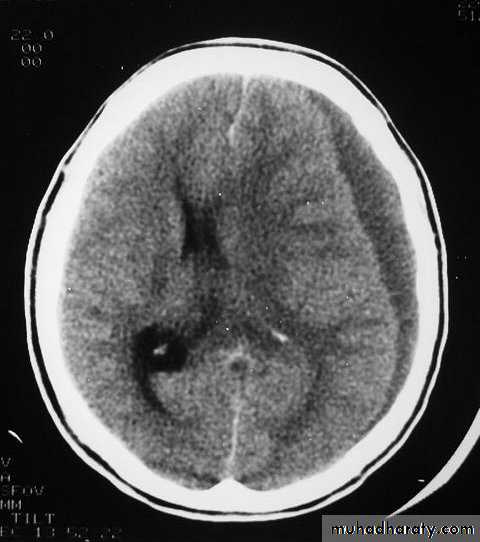

Медицинские аспекты и диагностика субдуральной гигромы мозга